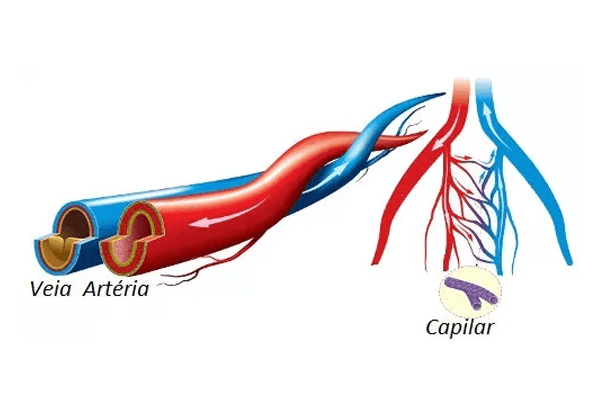

As veias, quando comparadas com artérias do mesmo calibre, possuem uma parede mais fina e um diâmetro maior e irregular. Além disso, elas apresentam válvulas que impedem o refluxo do sangue.

- Cavidade interna grande, o que reduz a fricção quando o sangue é transportado;

- Sangue sendo movido em baixa pressão;

- Não possuir muitos músculos e fibras elásticas associadas a elas;

- Presença de válvulas para prevenir que o sangue sofra refluxo quando transportado contra a gravidade.